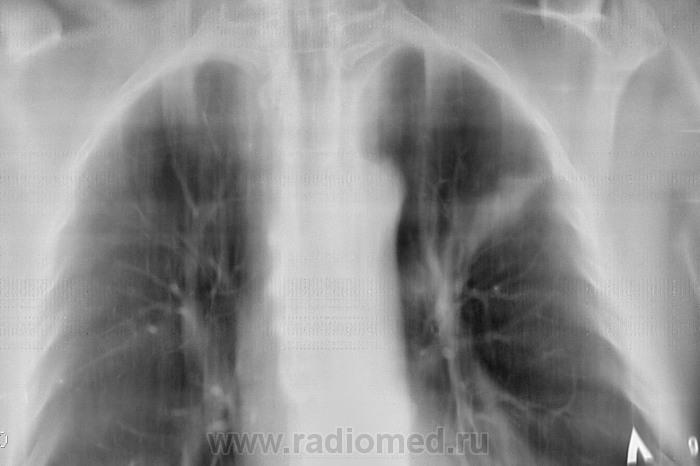

Направлен на рентгенографию ОГК с подозрением на пневмонию

Через 10 дней после проведения противовоспалительной терапии.

В корне как будто кругляк, но на тмг не видно, я бы онконасторожилась, возможно центральный рак растет

Левый корень уплотнен, расширен за счет головки, ателектаз С 2, динамики нет. Думаю, более вероятно образование. Интересен анамнез, иначе зачем бы его лечили 2 нед а\б.

2013 год - "флюшка" - норма.

Если в архиве год назад-норма,версия постттуберкулёзных изменений снимается.Онкология на первом месте.